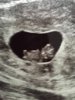

Hei alle sammen , har ikke vært her inne nå på en liten evighet fordi jeg merket at jeg ble mer redd for at noe skulle gå galt når jeg så folk forsvant fra gruppen osv .. Men i dag var jeg på ul og allt sto bare bra til , den lille krabaten beveget seg heftig og hjerte slo i hele 179 slag i minuttet

så føler ikke jeg har noen grunn til å uro meg lengre for at noe skal gå galt , ble bare flyttet en dag tilbake i følge han så er 9+1 i dag